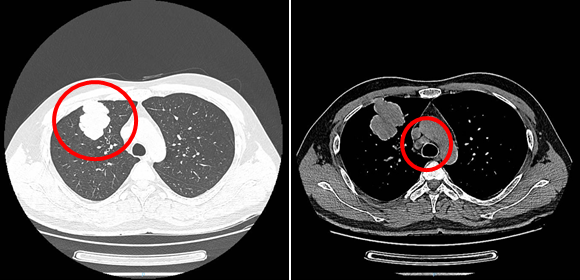

后续随访:ctDNA动态监测及影像学均未提示复发,持续随访中。

ctDNA动态监测至今持续阴性

影像学CT未提示复发